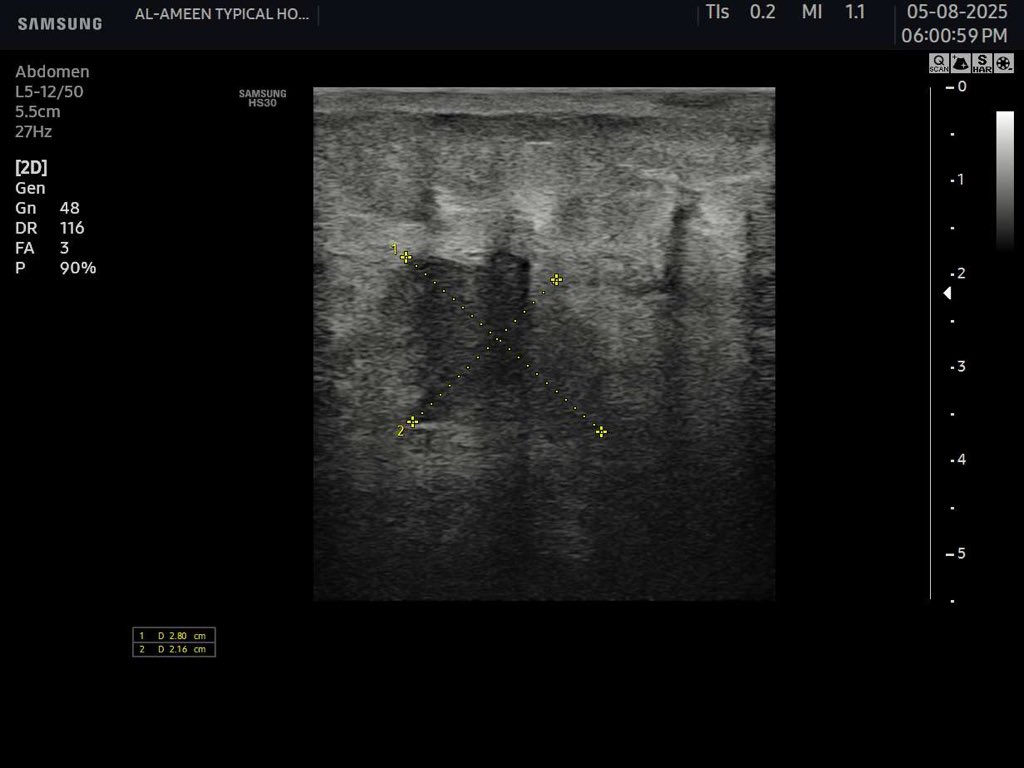

45 years female Presented with diffuse abdominal pain , persistent vomiting and bloody stool And a palpable abdominal mass seen to the RT of the umbilicus #EchoTech #Ultrasound #GIT

45 years female Presented with diffuse abdominal pain , persistent vomiting and bloody stool And a palpable abdominal mass seen to the RT of the umbilicus #EchoTech #Ultrasound #GIT

45 years female Presented with diffuse abdominal pain , persistent vomiting and bloody stool And a palpable abdominal mass seen to the RT of the umbilicus #EchoTech #Ultrasound #GIT